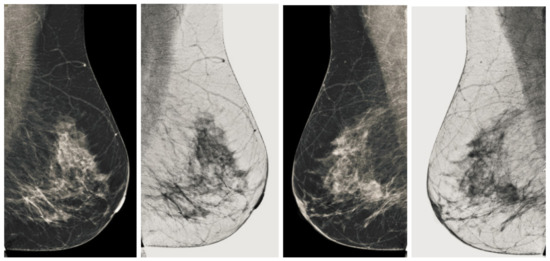

Figure 11.

Analysis of CC view of BI-RADS-3 mammogram images.

Figure 12.

Analysis of MLO view of BI-RADS-3 mammogram images.

We also measured the PSNR, the image contrast, and the EME of each category of databases, as we analyzed the image in terms of visual observation. The Table 3 shows the performance of our proposed image enhancement method. It can be seen from the Table 3 that our proposed method improved PSNR, contrast, and EME, and this also shows that our method can work on every category of BI-RADS. Because many techniques do not work on higher grade BI-RADS due to the complexity and the images are not of good quality. We obtained an average improvement in PSNR, contrast, and EME in the Table 4. For more observations, we analyzed the visual image of each category and we analyzed the CC and MLO of each category as shown in the Figure 7, Figure 8, Figure 9, Figure 10, Figure 11, Figure 12, Figure 13, Figure 14, Figure 15 and Figure 16. From the figures, every detail of image of every category can be observed, leading to better segmentation of the abnormal region. This image enhancement technique can be used as preprocessing steps for the detection of breast cancer. It is a very fast processing algorithm and it takes on 21.13 s. It gives opportunity to medical experts to analyze the mammogram images very quickly to propose the timely treatment.